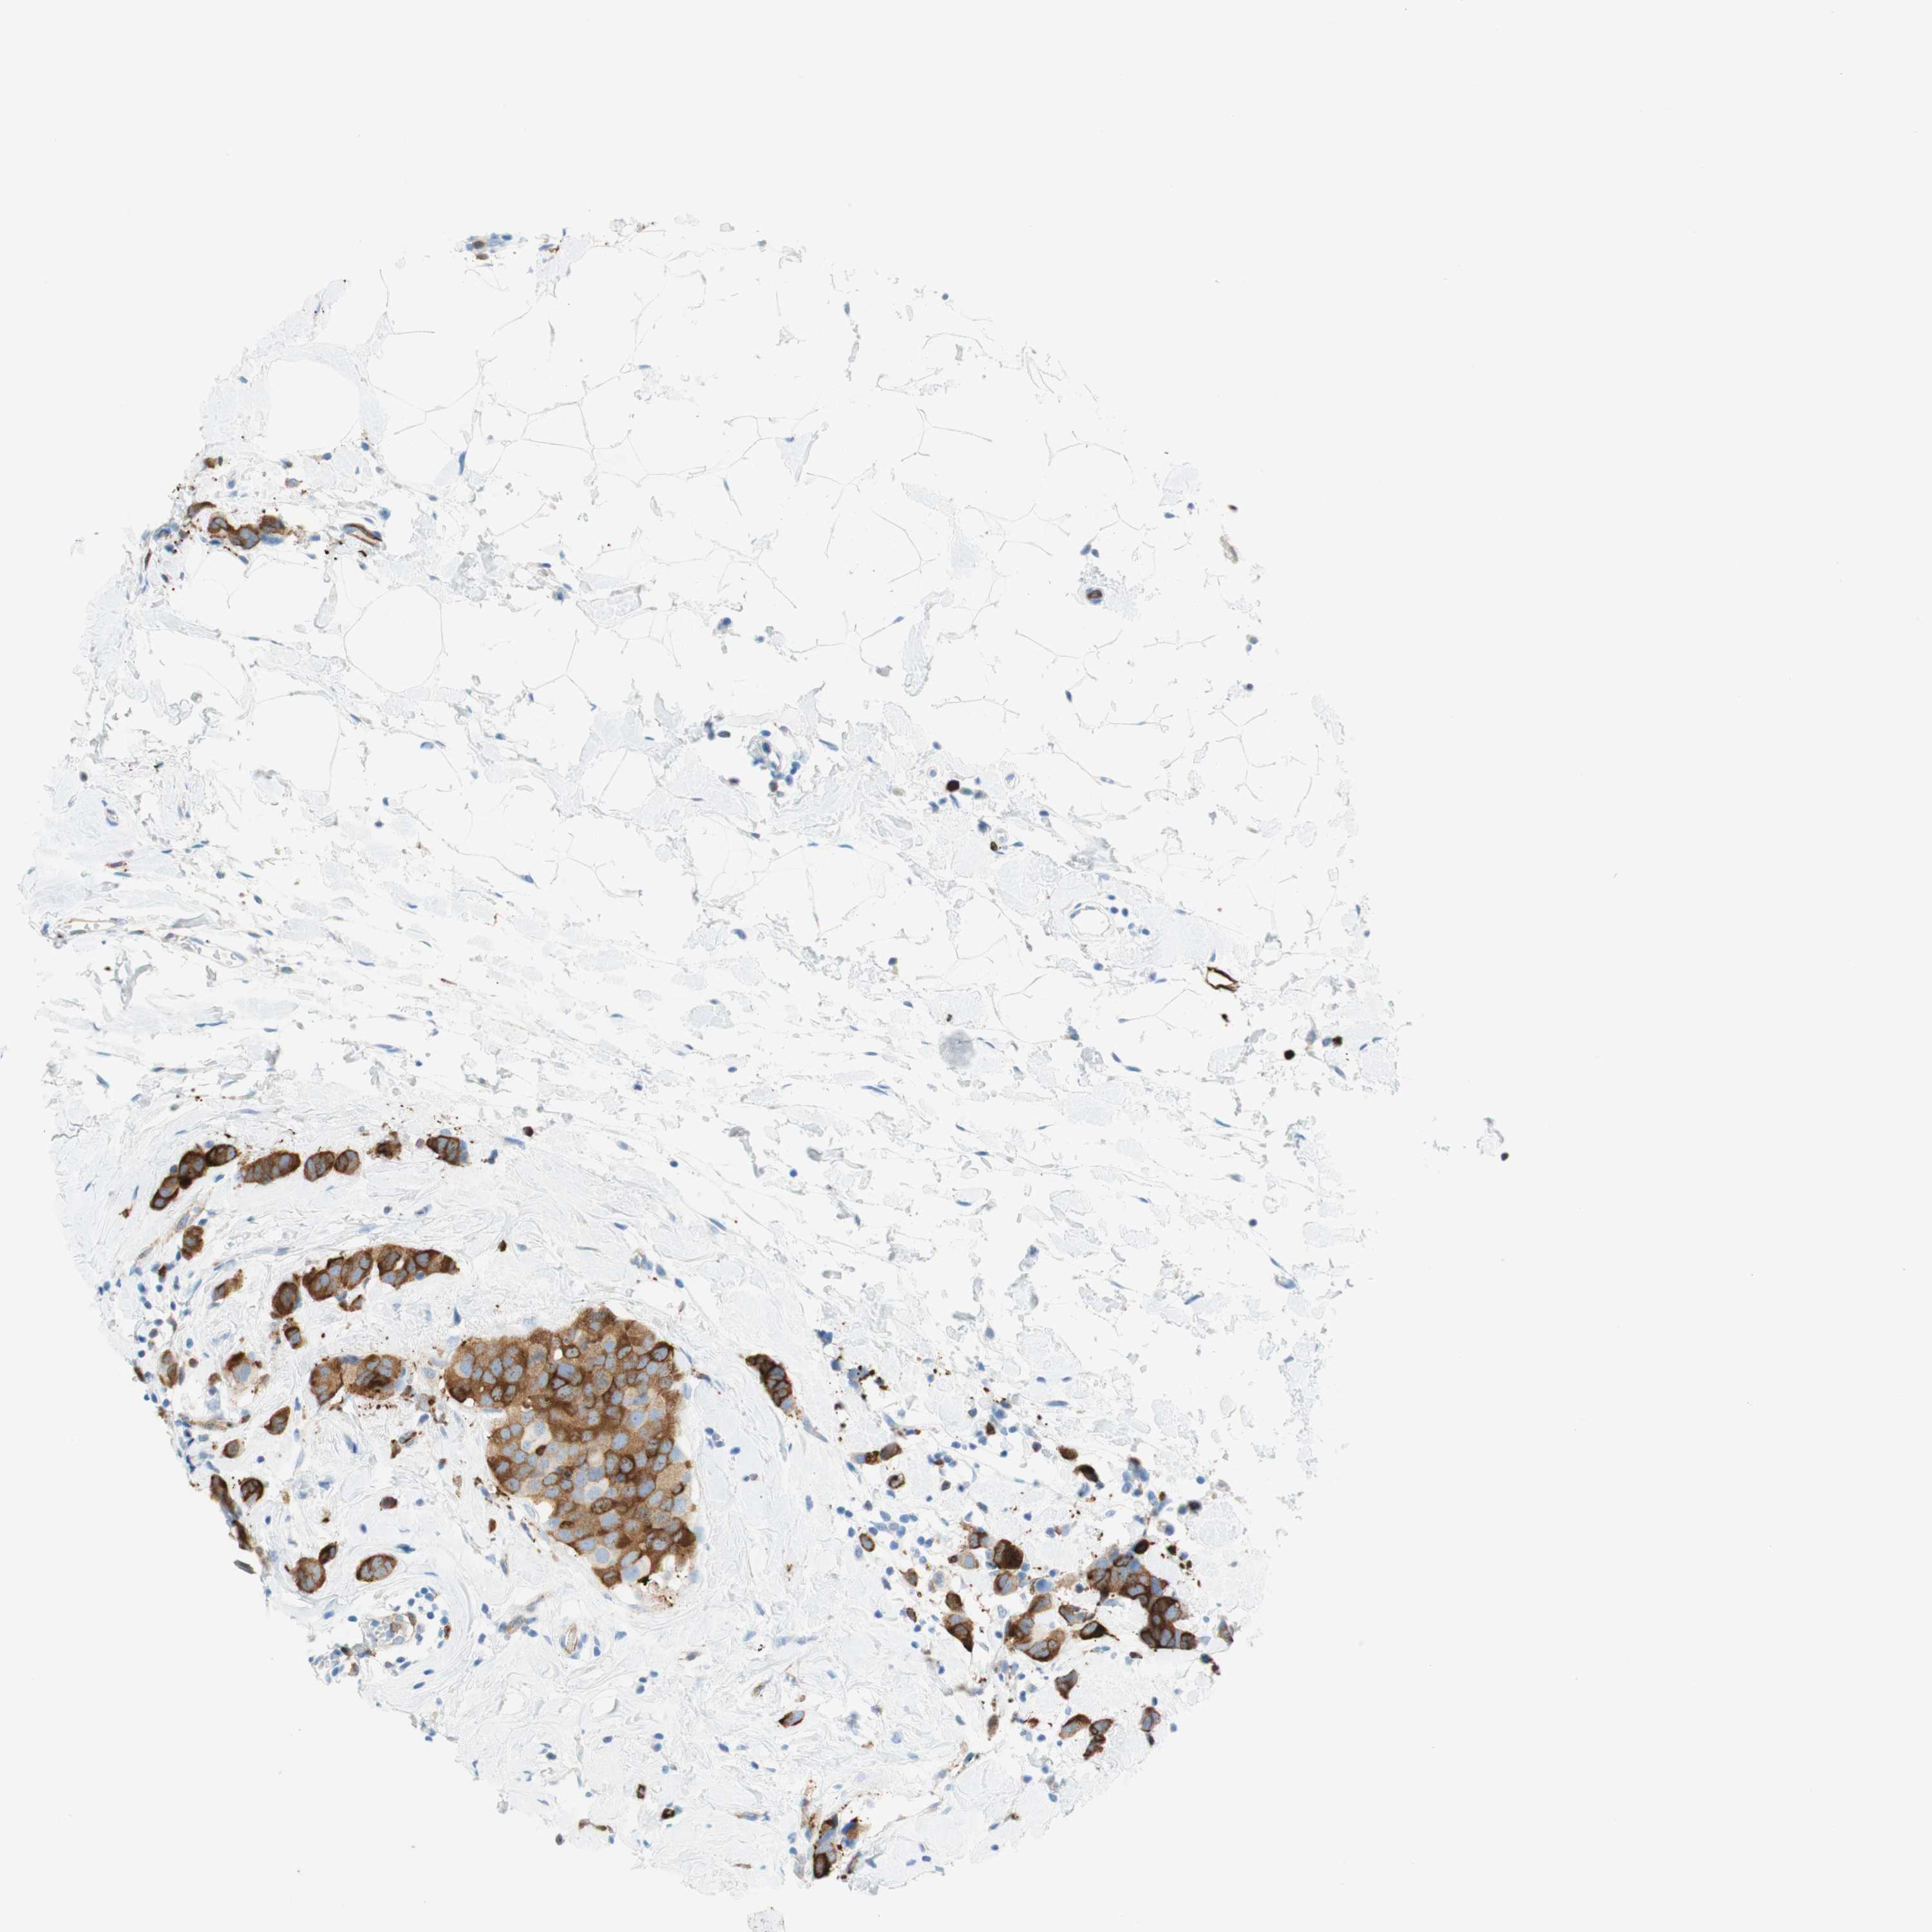

BRCA TCGA BRCA VALIDATION PROTEIN EXPRESSION

ANTIBODIES

AND

VALIDATION